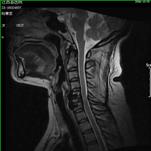

颈椎间盘突出、颈椎管狭窄——开展颈椎前路、后路手术治疗颈椎间盘突出、颈椎管狭窄,解除许多患者病痛,通过网上会诊方便患者,在家就能得到著名脊柱外科专家王少波教授诊治。

1).C4/5、C5/6间盘突出术前、 术后(C5椎体次全切除,钛笼植入)

2). C5-C6间盘突出术前、 术后(间盘切除,Cage植入)